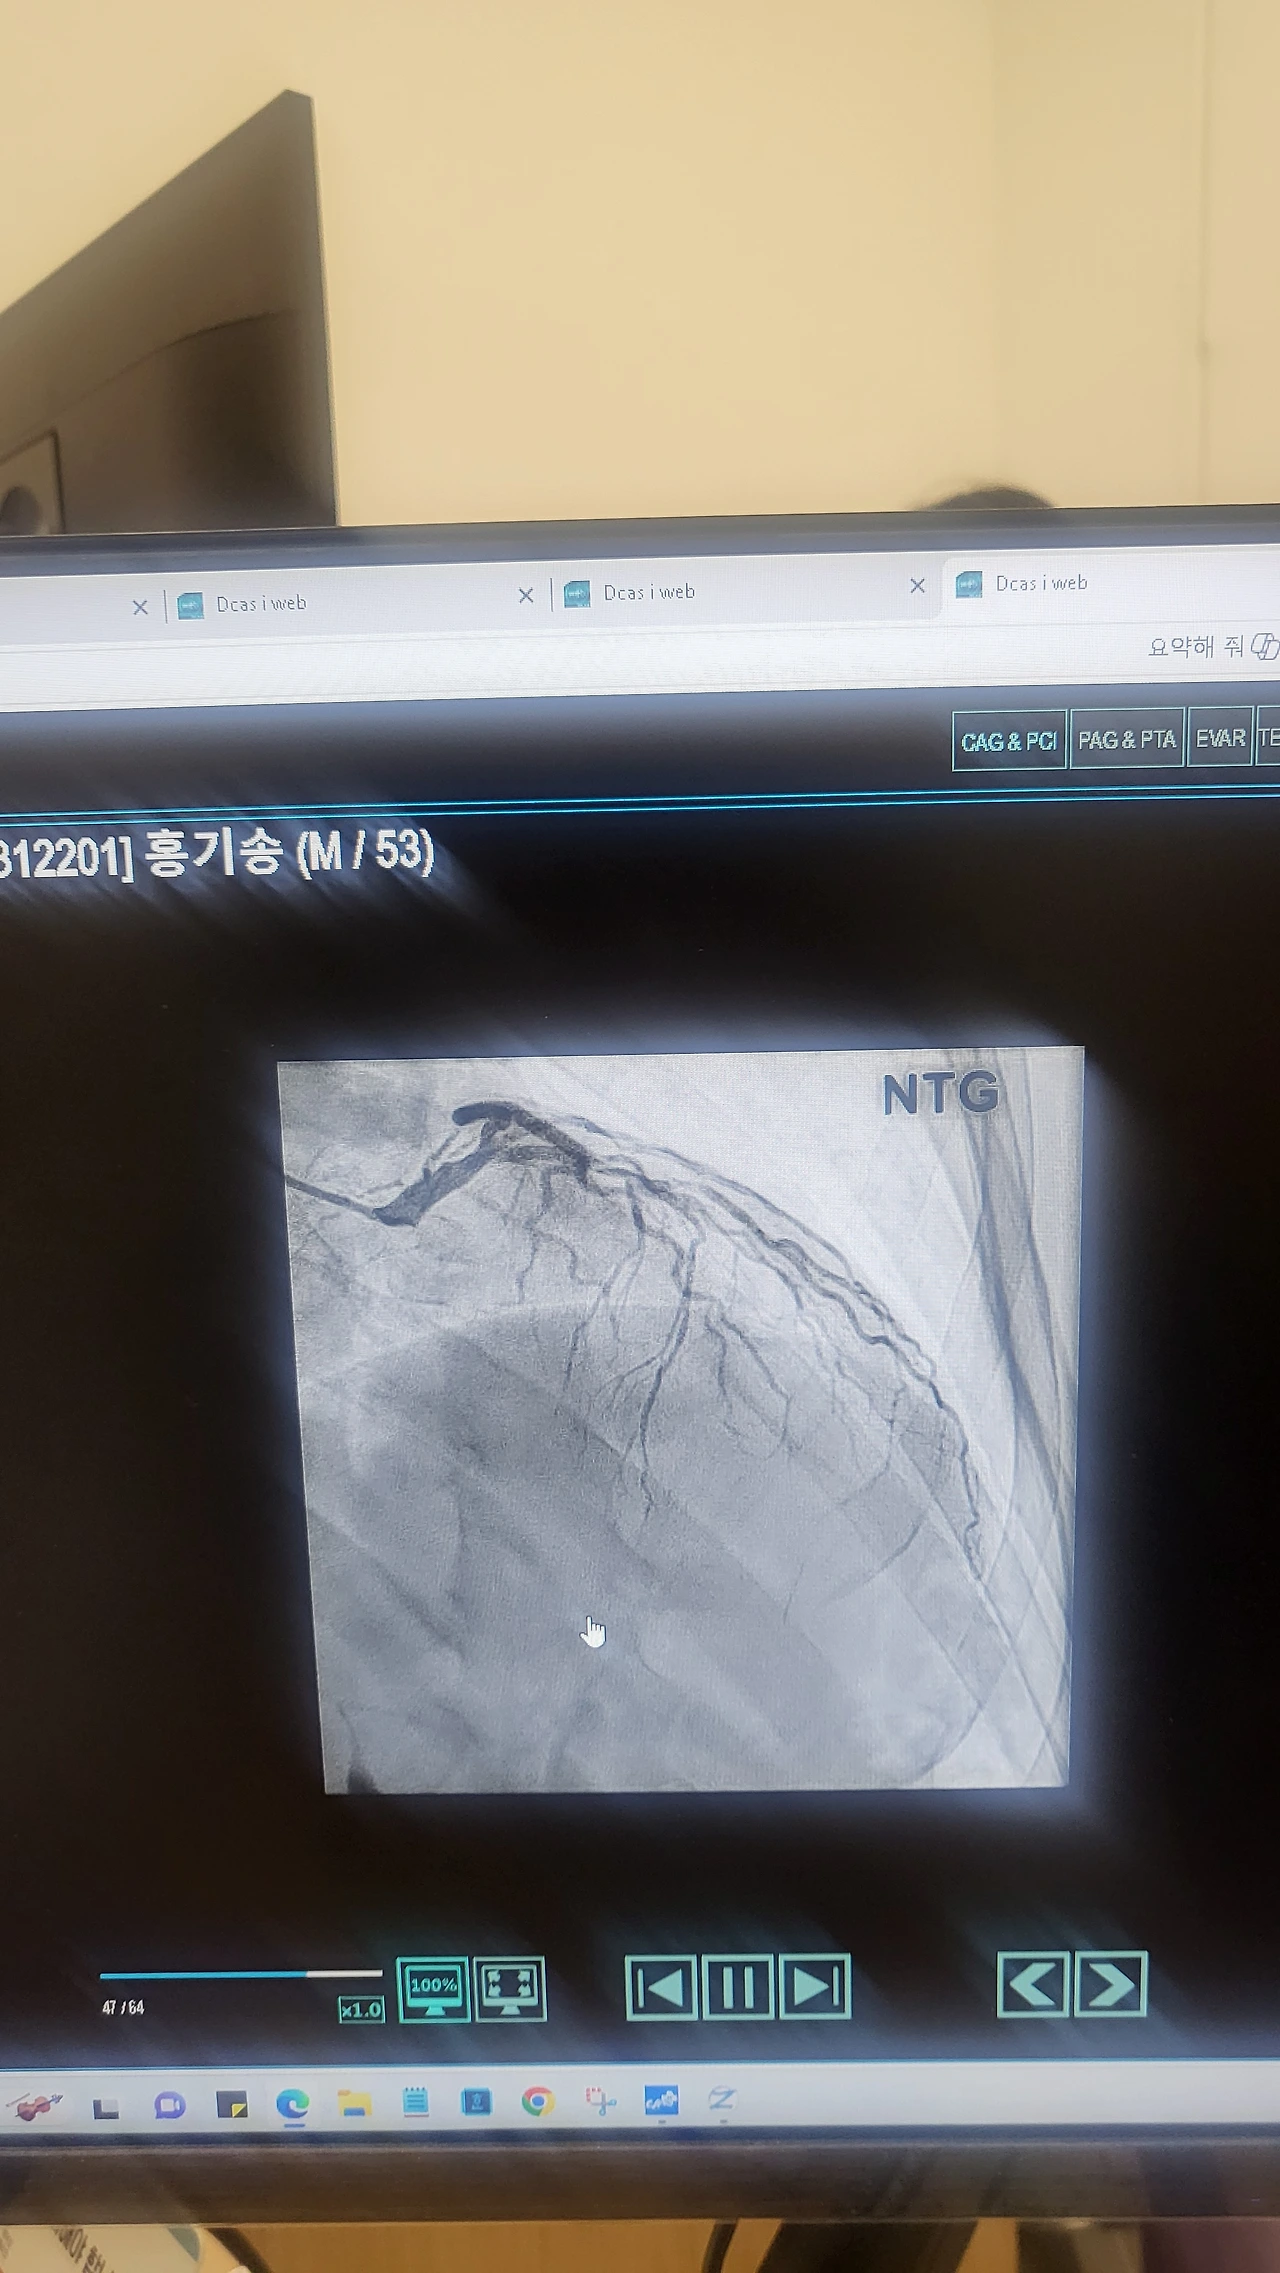

11시 20분 막힌 혈전이 뚫려 스탠트를 두 곳에 삽입한 시간, 정확히 2시간 10분, 내 뒤로 줄줄이 시술 예정이었던 환자들은 두 시간씩이나 기다려야만 했다. 의사는 시술결과가 좋다고 설명해 주었다. 막힌 곳이 뚫리지 않을 수도 있다며 시작했는데, 대단한 결과라며, 중환자실에서 경과 지켜보자고 했다.

가슴 위로는 정사각형의 CT기계가 심장으로 흐르는 혈관들을 계속 찍고 있었다. 누워있는 침대 옆으로 커다란 모니터가 심장 속 혈류의 흐름을 사진 찍듯이 선명하게 보여주고 있었다. 조영제가 들어갈 때 막힌 곳과 좁아진 곳의 위치가 정확히 드러났다. 마치 자동차 안에서 보는 내비게이션처럼, 얽혀있는 심혈관들의 혈류가 강물 흐르듯 흐르고 있었다.